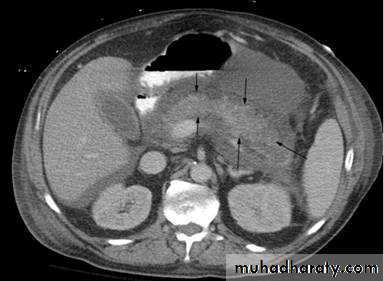

Contrast enhanced axial computed tomography (CT) shows non-enhancement of the swollen pancreatic body and tail (arrows) compatible with pancreatic necrosis.